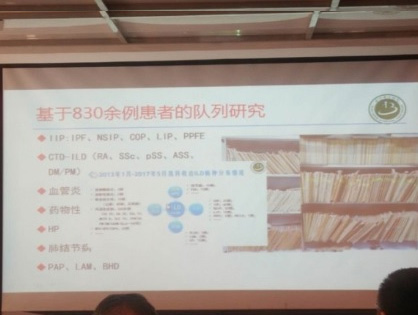

특발성폐섬유증과 같은 간질성폐질환은 예후가 좋지 못하다고 알려진 병입니다. 하지만 한약 치료를 통해 이 병을 극복하려는 노력이 진행되고 있습니다.